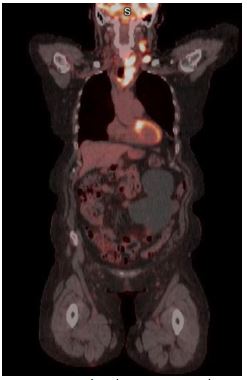

End of treatment PET scan revealed significant treatment response however there was evidence of residual asymmetric intense FDG uptake in the left thyroid gland (Figure 4). It was uncertain whether the PET findings represented inflammation due to Hashimoto’s thyroiditis versus residual lymphoma. Repeat biopsy of the left lobe showed patchy inflammatory infiltrate that may have been secondary to Hashimoto’s thyroiditis with no clear evidence of lymphoma (Figure 5). Due to the paucity of malignant cells in cases of TCHRBCL, residual lymphoma could not be excluded. Repeat PET scan 12 months later showed increase in size and uptake in her left thyroid gland. A repeat biopsy showed a lymphocytic thyroiditis picture and was negative for malignant cells.

Figure 4: Post treatment PET/CT showing improvement in lymph node uptake above the diaphragm with residual left lower thyroid lobe FDG uptake.